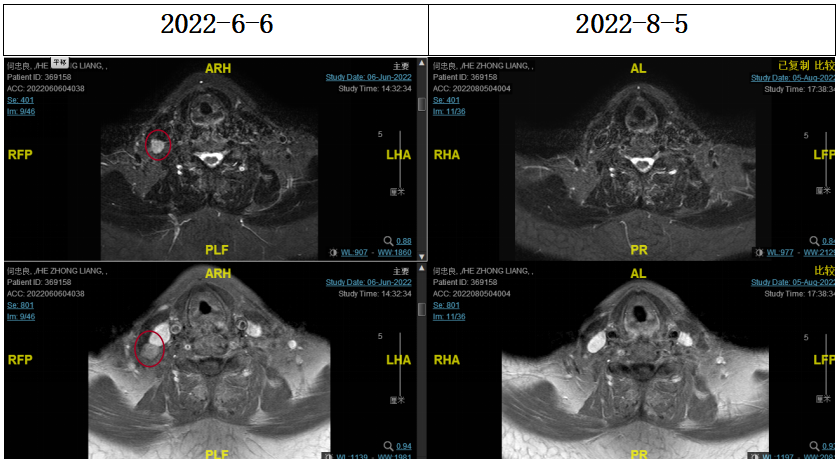

2022-06-29行鼻咽IGRT放疗:GTV1 68Gy/32f、GTV2 68Gy/32f、CTV1 60Gy/32f、CTV2 50.4Gy/28f。期间同步斯鲁利单抗+尼妥珠单抗+恩度治疗。

▌疗效评估

2022-08-05(放疗近结束)复查MR,疗效评价:CR。鼻咽部肿物及咽后转移淋巴结颈部转移淋巴结均达到CR。